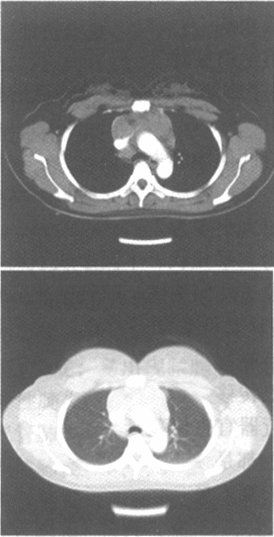

女,23岁,胸闷、气促1个月余,左锁骨上触及无痛性肿大淋巴结。胸部CT增强扫描片如图,最可能的诊断为

• A.淋巴瘤

• B.肺动脉栓塞

• C.右上肺肺癌

• D.非侵袭性胸腺瘤

• E.结节病